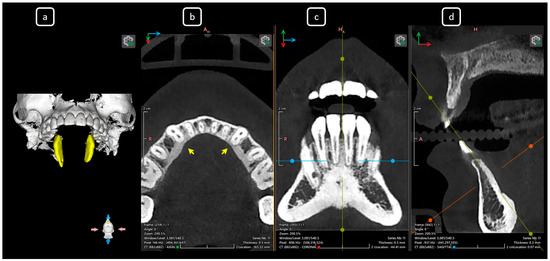

Cone beam computed tomography (CBCT) is a valuable diagnostic tool for evaluating the upper airway and maxillofacial region. This report demonstrates the clinical value of CBCT in identifying significant anatomical variations in endodontics, incidentally detected on a non-endodontic CBCT scan. A 23-year-old female patient underwent CBCT imaging at the Faculty of Dentistry-UJED to evaluate her upper airway. CBCT imaging revealed a unique, complex, and unusual anatomy of mandibular root canals, characterized by Vertucci’s type III root canals in the anterior sextant and co-occurrence of bilateral C-shaped mandibular second molars (type C2 according to Fan’s classification). No therapeutic interventions were initiated due to the patient’s asymptomatic status. CBCT imaging is a valuable tool for integrated diagnostic approaches, underscoring its role in thorough patient management. The integration of multidisciplinary interpretation of CBCT data can enhance diagnostic accuracy and optimize patient records and management, emphasizing the importance of collaborative efforts between radiologists, clinicians, and endodontists. Documenting and sharing such findings can increase awareness of rare anatomical variations, facilitating detection and contributing to medical knowledge. Full article

Figure 1